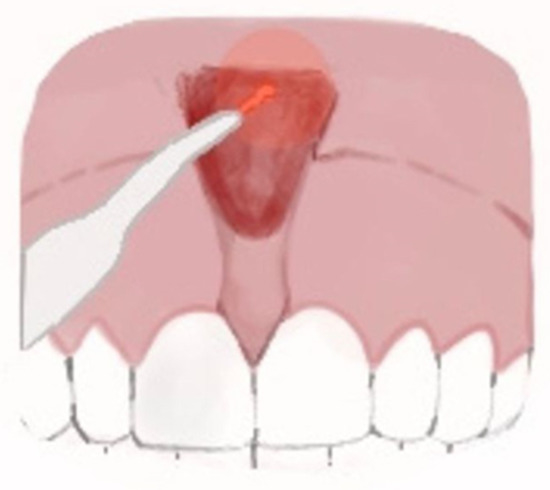

Others experience the taut, fibrous, papillary, or transpapillary insertion interincisional frenulum more frequently, which has a broad triangular upper insertion known as the tecto-labial frenulum. This kind of frenulum is regarded as a genuine dysontogenic manifestation of fetal frenulum persistence after birth [5]. The surgical approaches that are currently in use are: (a) frenectomy or excision, which involves complete removal of the frenulum; (b) frenulotomy, which involves partial removal of the frenulum (Figure 2); (c) apical repositioning of the frenulum [9,10,11].

Figure 2.

Frenulotomy: (A) Hypertrophic superior median frenulum with insertion on the interincisive papilla; (B) partial thickness incision disengages frenulum and muscle fibers and does not involve the periosteum; and (C) suture and apical repositioning on the labial side.